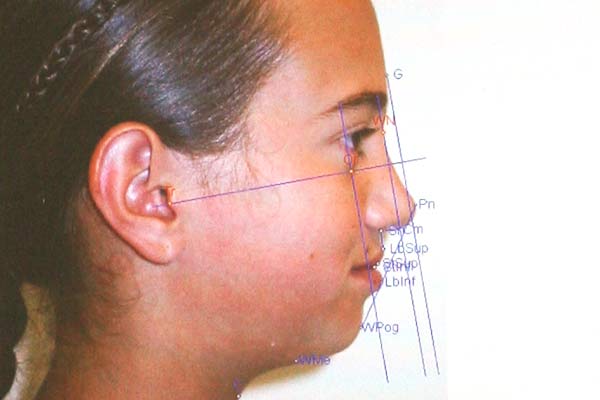

Digitale Fotoanalyse

Profil- und Enface-Fotos des Gesichtes sind für das Studium der Profil- und Lachlinie für ästhetische Überlegungen erforderlich, da die Veränderungen der Zahnstellung im Frontzahnbereich auch Einfluss auf das Lippen- und Gesichtsprofil mit sich bringen.

Zu Beginn der Behandlung werden vom Patienten mit einer hochauflösenden, digitalen Fotokamera

Fotostat-Aufnahmen vom Gesicht, Profil und den Zähnen erstellt und am

Computer ausgewertet. Die Fotos werden dabei am aufrecht sitzenden Patienten in ungezwungener Lippenhaltung angefertigt.

Mit Hilfe der digitalen Fotoanalyse werden das Gesichtsprofil, der Lippenverlauf, die Lachlinie und Gesichtsasymmetrien (z.B. Nasen- und Kinnabweichungen) bewertet. All diese ästhetischen Überlegungen sind erforderlich, da die Veränderungen der Zahnfehlstellungen im Frontzahnbereich auch

Einfluss auf das Lippen- und Gesichtsprofil mit sich bringen.